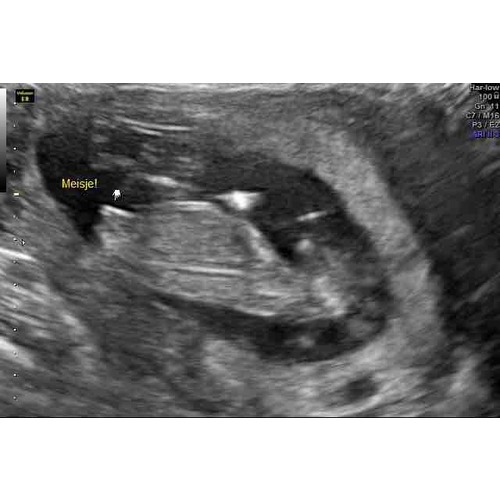

Hier de 3 streepjes bij 15 weken en 3 dagen